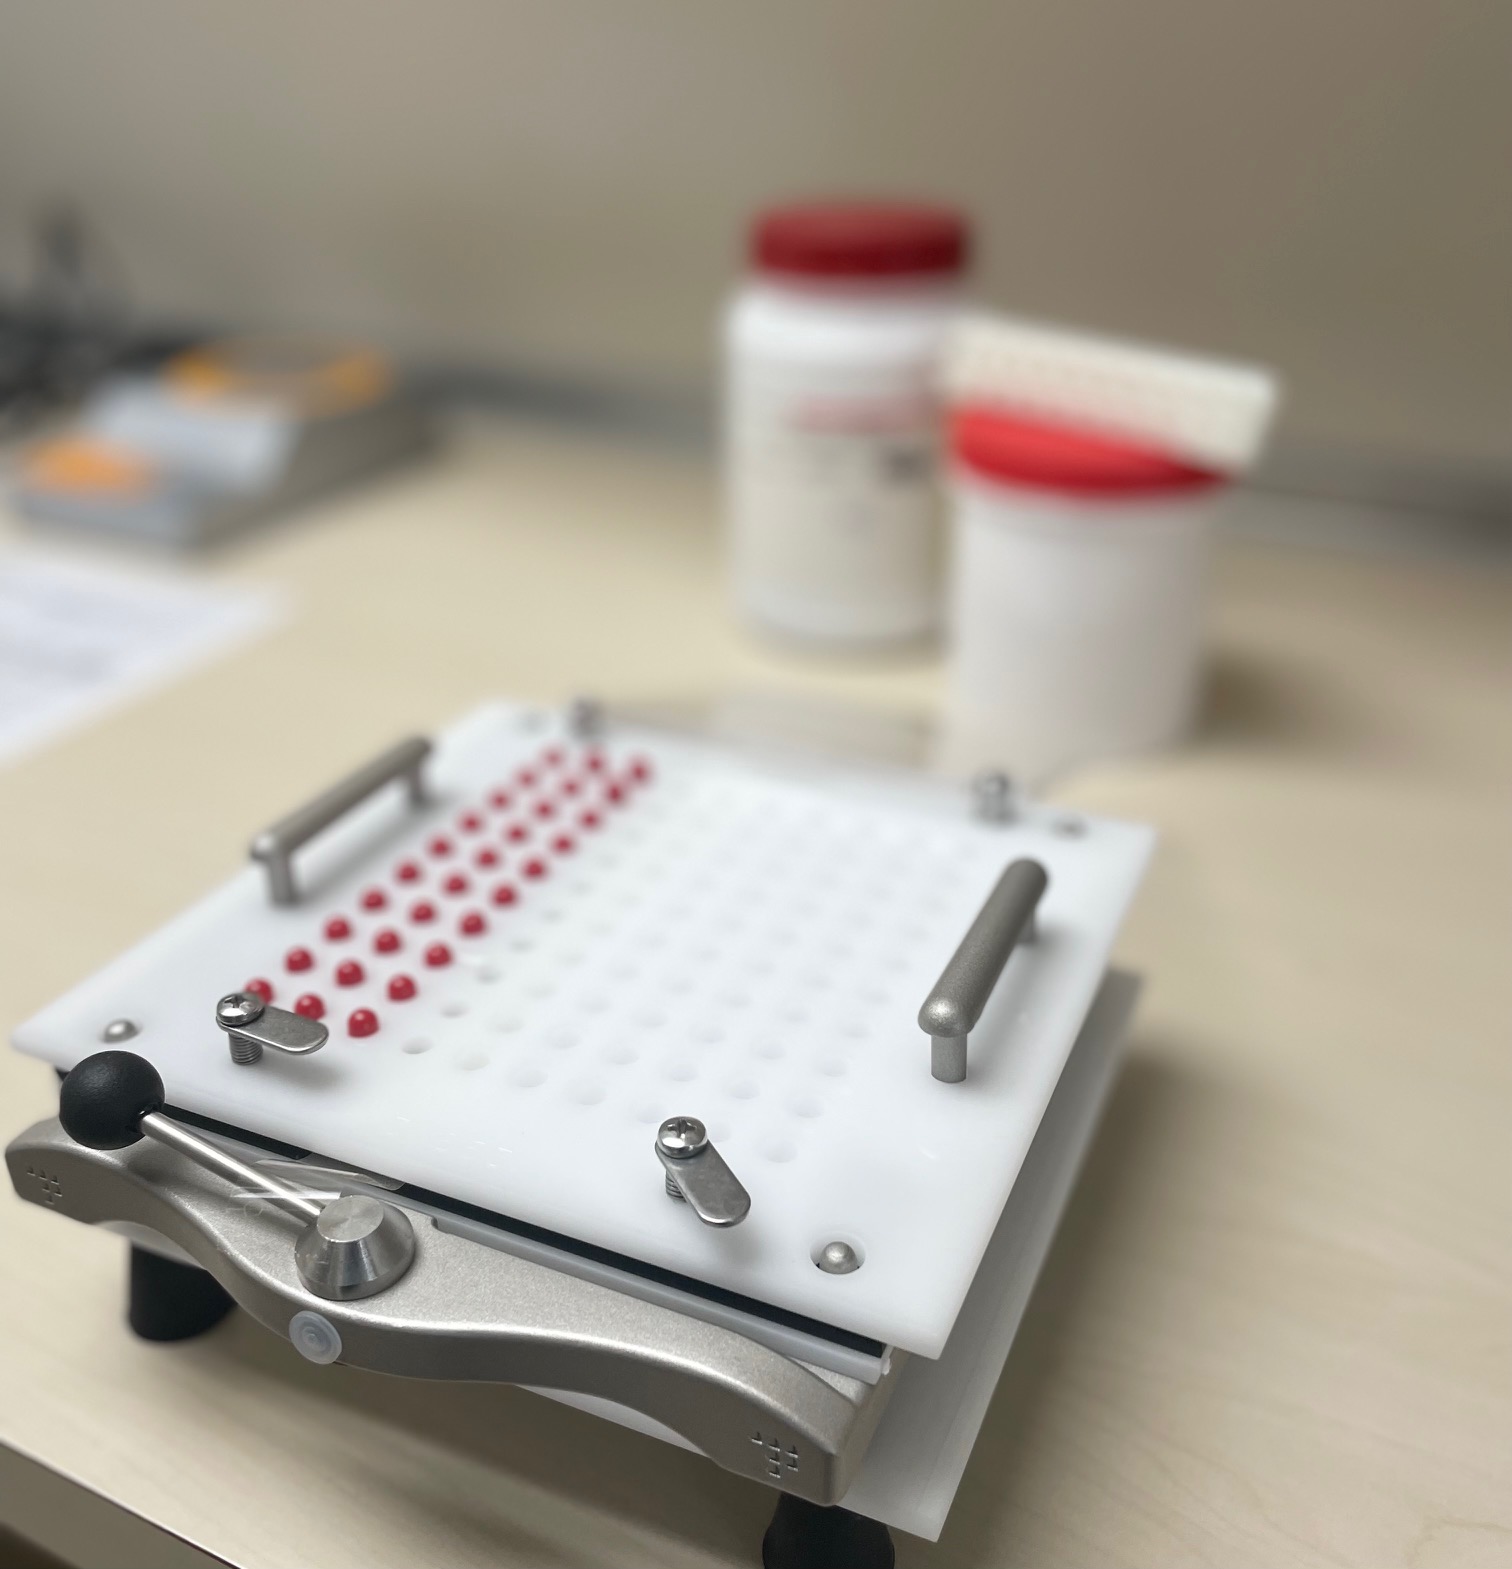

Preparación de la medicación en Sistemas personalizados de dosificación; organizamos tu medicación, la revisamos y reemblistamos para mejorar

el cumplimiento y adherencia a los tratamientos asegurando optimizar la eficacia de estos.